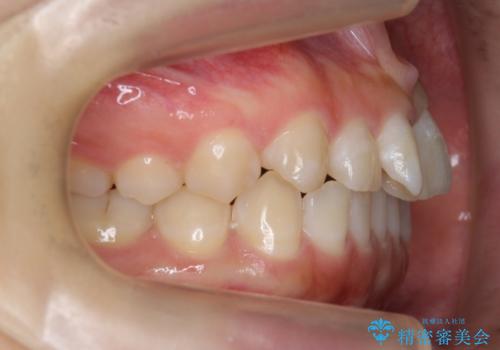

前歯のねじれ 乳歯を残して矯正治療

- 前歯のねじれを気にして来院。

左下に乳歯が残っていましたが、被せ物に穴が空いている状態でした。

乳歯は抜かずに保存的な治療を行いました。

上下の正中が1本分ずれていましたが、ちょうど1本分で目立たず、また、右下の歯が生まれつき少ないことを利用して、最小限の歯の移動にとどめました。